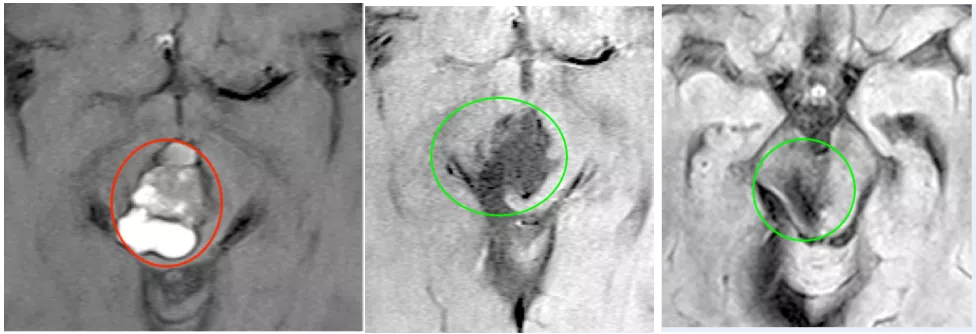

图:磁共振图像显示出血没有明显的病理原因,(a)T2加权(b)T2加权。

术前MR:脑干中脑巨大占位并发出血